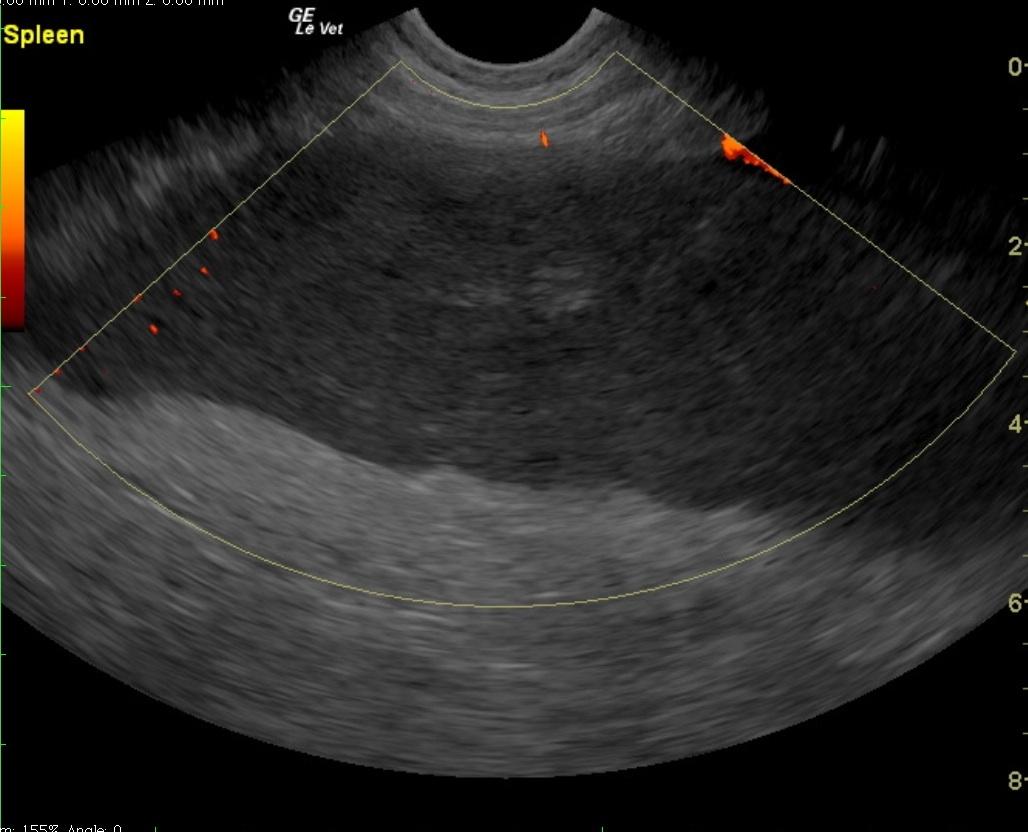

A 6-year-old intact male English Bulldog was presented for 2-3 days of intermittent vomiting and lethargy. Physical exam found the patient to be tachycardic with pale mucous membranes and a palpable mass in the abdomen. Serum biochemistry revealed elevated alkaline phosphatase, hypernatremia, and mild hypochloremia. On CBC, a decreased HCT in conjunction with a high MCV was noted, in addition to a neutrophilia, monocytosis and thrombocytopenia. No abnormalities were noted on thoracic radiographs. Abdominal radiographic findings revealed a loss of contrast in the cranial abdomen, with the possibility of a splenic mass. Radiographic Interpretation showed marked splenomegaly strongly suspected to be secondary to torsion, although accompanying infiltrative or neoplastic pathology could not be ruled out. The small volume of peritoneal effusion and inflammation was likely secondary to the splenic pathology. Thoracic radiographs showed mild microcardia and under perfused pulmonary vasculature in support of hypovolemia. Atypical intrathoracic fat distribution was considered to be incidental in this dog. This dog had multiple hemivertebrae.